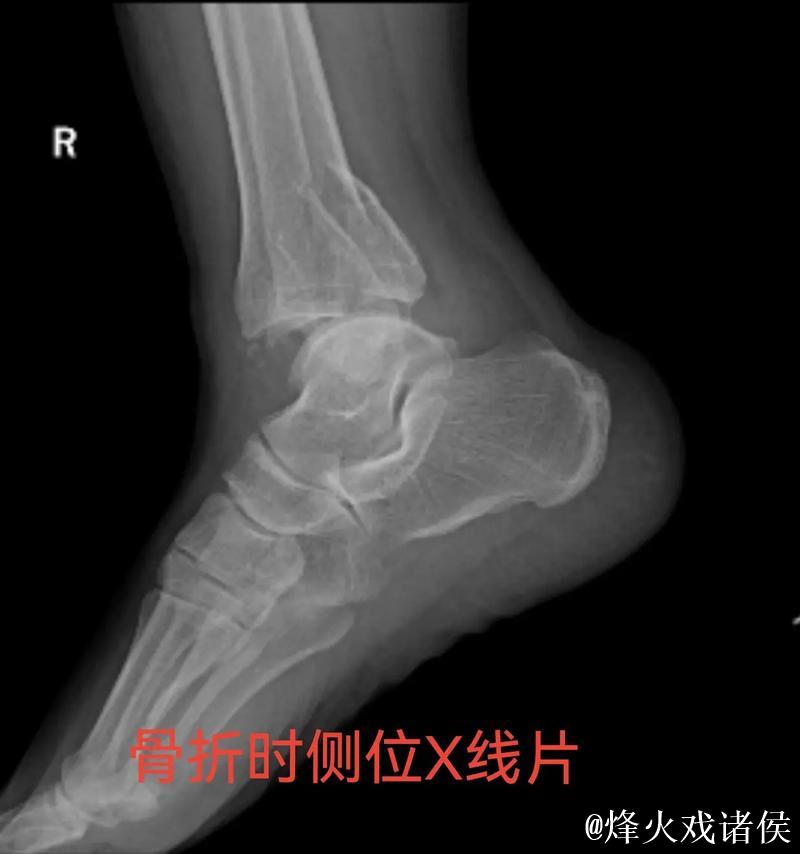

伤情解析 右踝三角韧带与腓骨骨折意味着什么

很多人在看到“右踝三角韧带断裂 右侧腓骨骨折”这样的医学表述时,只会感觉到“很严重”三个字,却未必真正理解其中的含义。踝关节三角韧带位于脚踝内侧,是一个由多条韧带组成的“组合体”,主要负责保持踝关节的内外稳定,防止小腿和足部出现异常翻转。当运动员在高速突破、急停、变向或落地时,如果脚踝遭遇过度外翻或扭转,三角韧带就可能被强行拉伸甚至撕裂。完全断裂不仅会造成剧烈疼痛,还会直接破坏踝关节的稳定性,使人几乎无法正常负重行走。与之同时出现的右侧腓骨骨折,大多与剧烈外力撞击或扭转应力有关。腓骨虽然不像胫骨那样承担大部分体重,但在踝关节的力学链条中起到重要支撑和协同作用。当韧带与骨骼在一次意外中同时受损,就意味着踝关节遭遇了极端应力,恢复与康复的难度成倍增加。

医学视角下的恢复周期 手术康复和不确定性

对于三角韧带断裂与腓骨骨折这种组合伤情,医学团队通常会综合评估踝关节稳定性、骨折位置与移位程度、软组织损伤范围,来决定是否采用手术治疗。若存在明显关节不稳或骨折移位,往往需要通过钢板、螺钉或钉棒内固定来重建骨性与韧带结构。在此之后,便是漫长而细致的康复周期。一般而言,骨折在数周内可以初步愈合,但韧带修复与功能恢复远比“骨头长好”更复杂。康复过程需要一套循序渐进的计划:早期的消肿与被动活动、中期的肌力与本体感觉训练、后期的专项运动模拟。每一个阶段若处理不当,都可能导致关节僵硬、力量不足或反复崴脚等后遗症。对职业运动员来说,问题不仅是“能不能走路”,而是“能不能继续高强度比赛、能不能保持原有水平”。任何轻微的落差,都可能在激烈竞争的职业舞台上被放大。